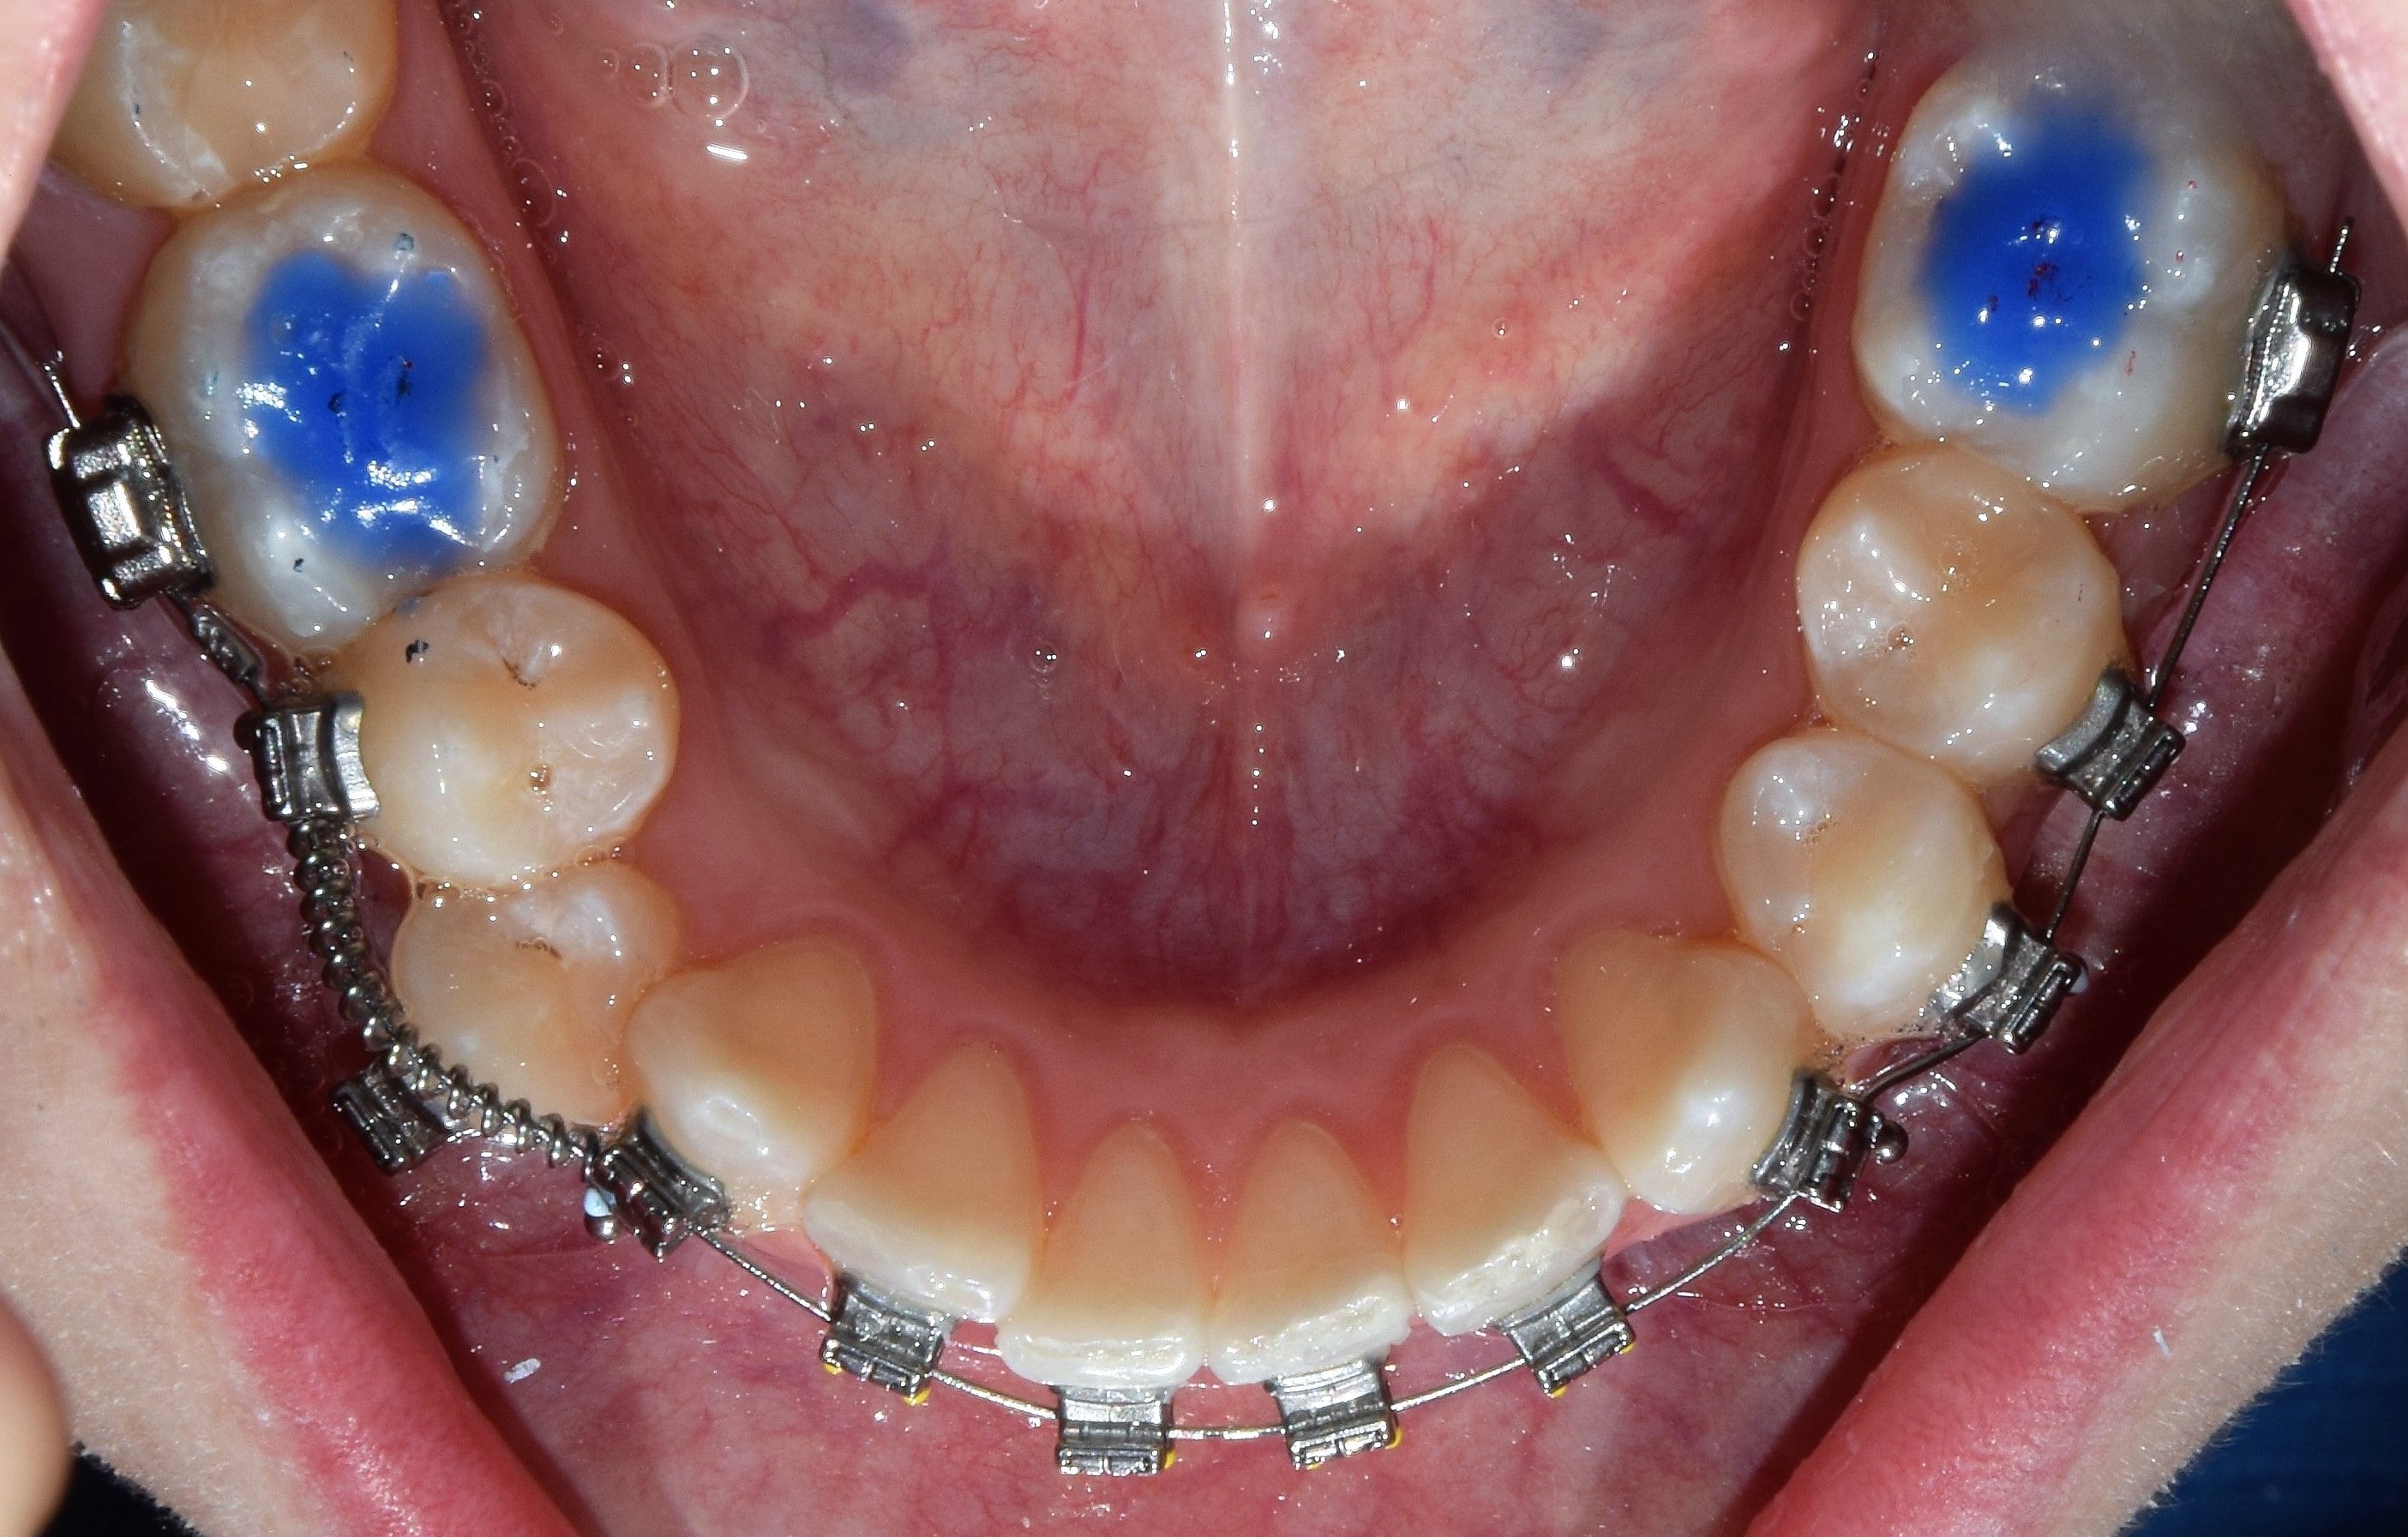

Harapásemelők alatt a fogak rágó (oldalsó fogaknál), vagy belső (elülső fogaknál) felszínre ragasztott, színes tömőanyagból készült blokkokat értjük. Ezeknek köszönhetően eltávolodik egymástól az alsó felső fogív, és mivel a fogak nem érintkeznek egymással, gyorsabb és fájdalommentesebb a fogmozgatás. További nagy előnyük, hogy mivel az alsó-felső fogív a kezelés elején csak a harapásemelőkön érintkezik egymással, így a bracketekre nem lehet ráharapni, azok nem esnek le. Segítségünkre vannak mind a nyitott-, mind a mélyharapás kezelésében. Minden kezelésemnél használok harapásemelőt. Eltávolításuk speciális fúrókkal történik, így a fogzománcot nem sértjük meg.